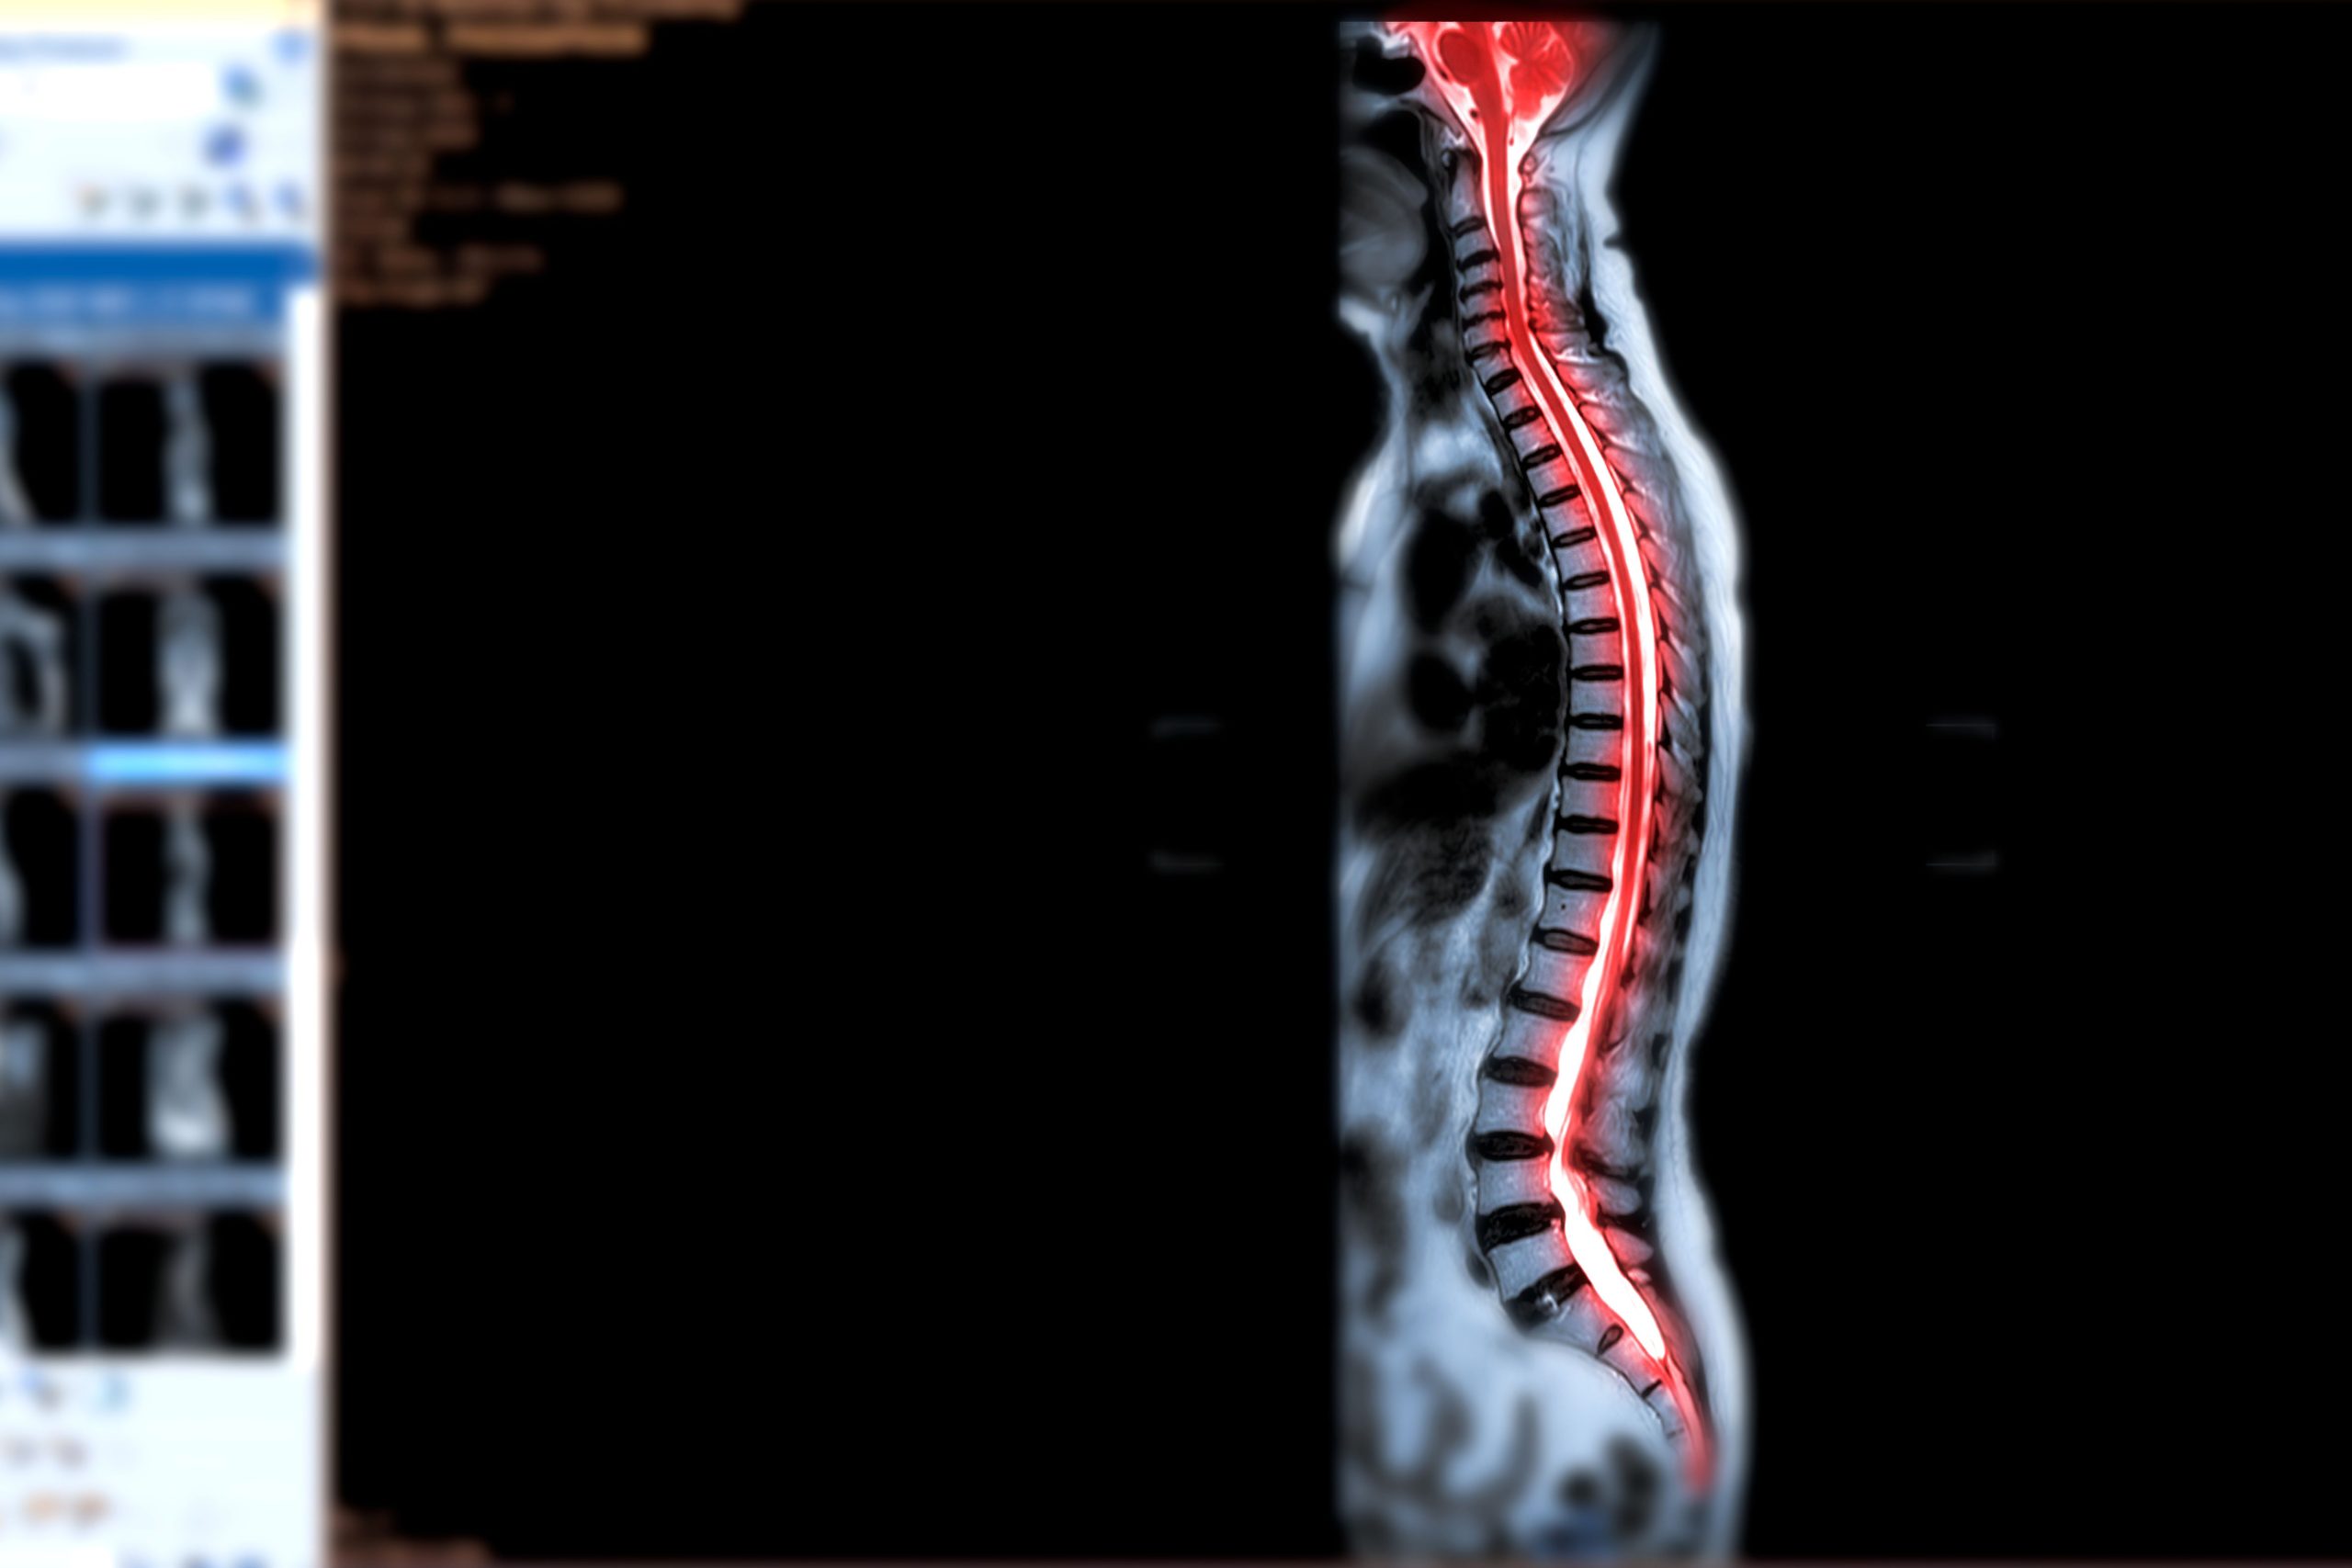

Ogni anno nel mondo si verificano tra i 10,4 e gli 83 casi per milione di abitante di lesione spinale. Se nei Paesi sviluppati le lesioni spinali sono per lo più legate a ragioni traumatiche, in quelli non sviluppati esistono molti casi non traumatici, dovuti a condizioni degenerative, a tumori, a patologie vascolari, a infezioni e a infiammazioni.

La riabilitazione nei pazienti con lesione spinale non traumatica è particolarmente importante e necessita di un approccio altamente personalizzato, che tenga conto anche della causa della lesione.